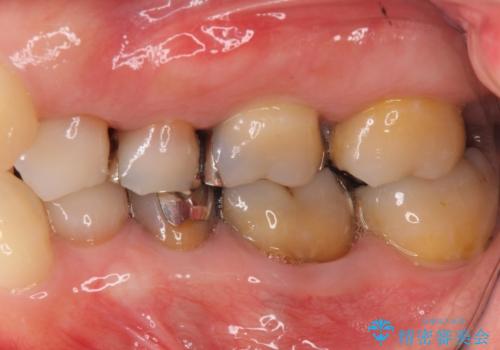

下の銀歯をセラミックに 虫歯治療

- 左下の銀歯を白くしたいと来院。

左下5番は根管治療のやりなおし、左下6番は上物(クラウン)のやり替えのみを行いました。

左下7番はアマルガムが入っていたため、ご希望によりセラミックインレーで治療を行っています。

- 44万円(内訳 左下7:emaxプレスインレー 左下6:仮歯、ジルコニアクラウン 左下5:精密根管治療再治療、ファイバーコア、仮歯、ジルコニアクラウン)費用は治療当時の料金となります